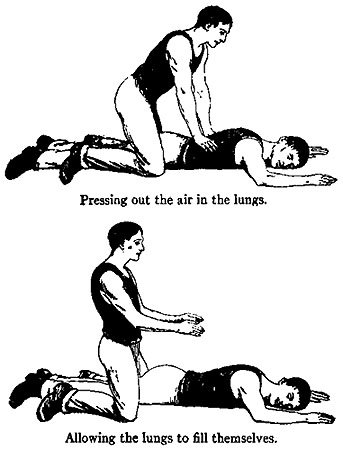

328 The New Method of Artificial Breathing

Onions, especially the milder and larger ones, are an excellent and wholesome vegetable, containing small amounts of starch, although their pungent flavor, due to an aromatic oil, makes them so irritating to some stomachs as to be quite indigestible.